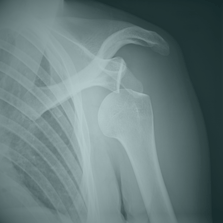

Dislocaciones

Origen: Ocurren cuando un hueso se desplaza de su articulación debido a caídas o movimientos bruscos, afectando comúnmente hombros, codos y rodillas.

Tratamiento: La prioridad es estabilizar la articulación sin intentar reducirla en el campo. Se utiliza inmovilización con vendajes o férulas, manteniendo la articulación en su posición actual. Es crucial controlar el dolor y verificar la circulación.